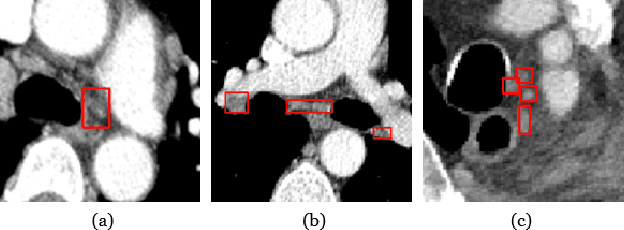

Abstract:Accurate lymph node detection and quantification are crucial for cancer diagnosis and staging on contrast-enhanced CT images, as they impact treatment planning and prognosis. However, detecting lymph nodes in the mediastinal area poses challenges due to their low contrast, irregular shapes and dispersed distribution. In this paper, we propose a Swin-Det Fusion Network (SDF-Net) to effectively detect lymph nodes. SDF-Net integrates features from both segmentation and detection to enhance the detection capability of lymph nodes with various shapes and sizes. Specifically, an auto-fusion module is designed to merge the feature maps of segmentation and detection networks at different levels. To facilitate effective learning without mask annotations, we introduce a shape-adaptive Gaussian kernel to represent lymph node in the training stage and provide more anatomical information for effective learning. Comparative results demonstrate promising performance in addressing the complex lymph node detection problem.